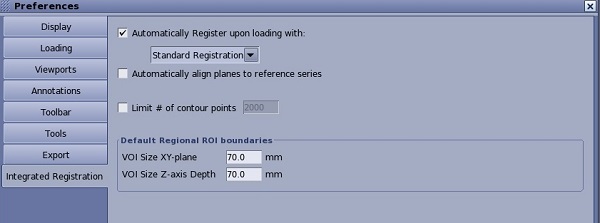

| Auto Registration

| Use to perform an automatic registration.Click the arrow to view a list of automatic registration algorithms available for a given Reference and Registered series pair. Note that registration algorithms are defined for Body and Neuro use cases (anatomies or protocols). |